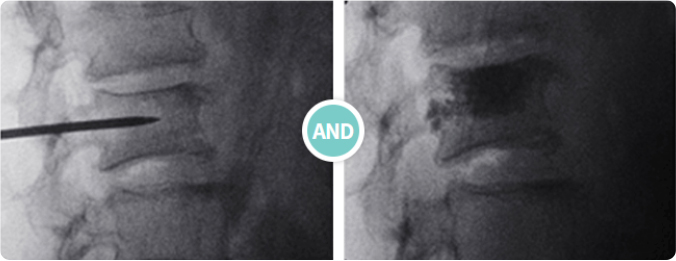

풍선성형술

척추의 퇴행성 변화로 좁아진 척추 신경 통로(추간공)에 풍선 확장 기능이 있는 특수한 카테터를 꼬리뼈 부위를 통해 삽입 후 병변 부위에 도달하여 풍선의 확장과 수축의 원리를 이용해 좁아진 추간공을 넓혀 신경근 주변의 유착을 풀어주고 신경치료 약물을 주입하여 치료하는 시술입니다.

시술 전 추간공 협착

풍선 이용한 추간공 확장 시술

시술과정